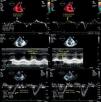

other parameters for characterization of RV morphology and function: in apical 4-chamber view, diastolic RV diameters (Figure 1) and the gradient between the right ventricle and right atrium in systole (RV/RA gradient). In parasternal short-axis (at the level of the papillary muscles): left ventricular diastolic diameters, to calculate the diastolic left ventricular eccentricity index (LVEI) (Figure 3).

Figure 3.Echocardiographic measurements in a pulmonary hypertension patient at rest (left) and at peak exercise (right); top – diastolic left ventricular eccentricity index; bottom – RV/RA gradient. D1 and D2: left ventricular diameters; LV exc index: diastolic left ventricular eccentricity index; RV/RA grad: right ventricular/right atrial gradient in systole.